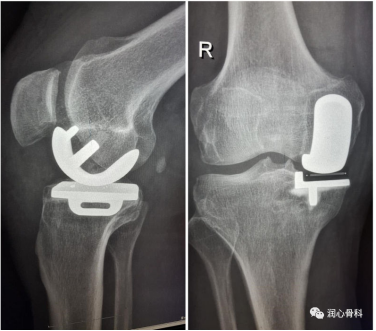

2.对于年龄较大、体重较重的患者,如果单纯内侧间隙消失但外侧间隙正常时(或者外侧间隙消失,内侧间隙正常),我们可以采用单髁置换术。

当膝关节内外侧间隙一侧消失另外一侧也变窄或消失时,就需要全膝关节置换了。